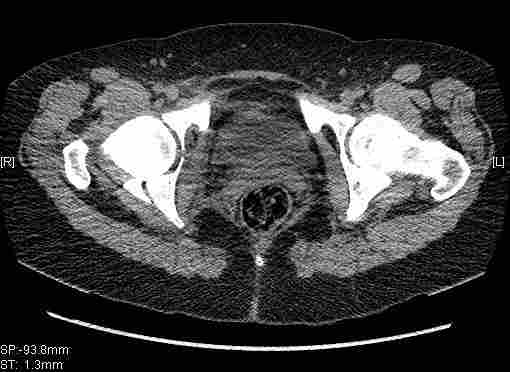

Остальные срезы.